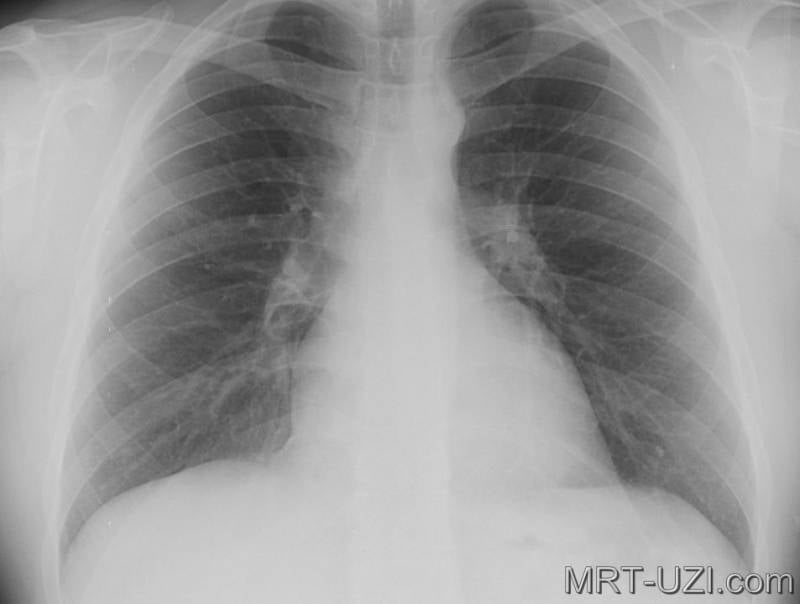

Нормальная рентгенограмма легких: что нужно знать

Раздел: Мудрость в объективе